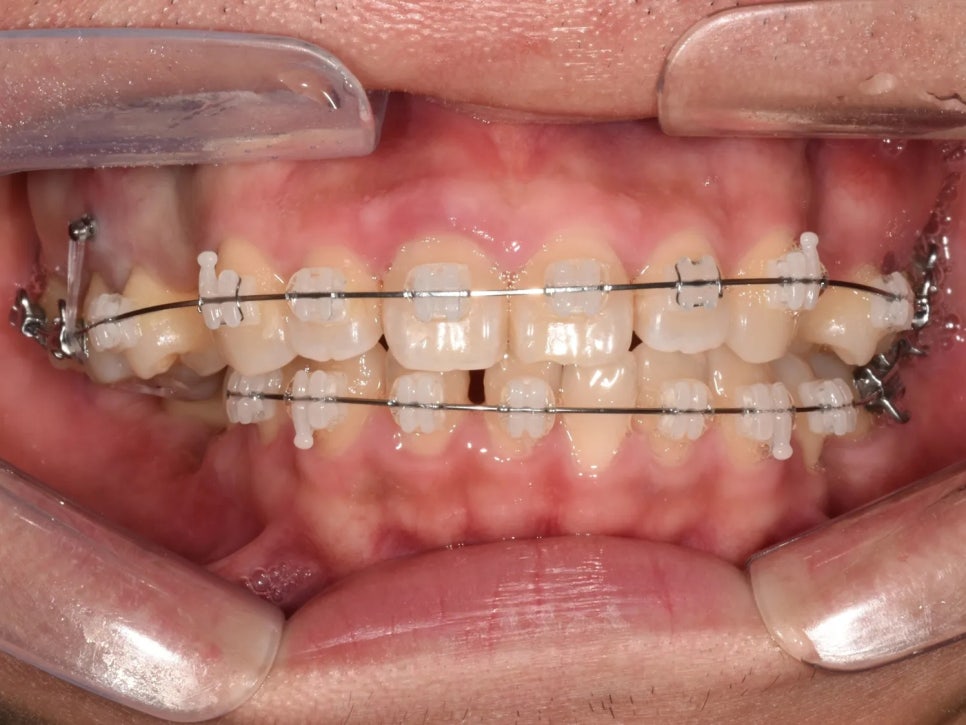

치료 과정 ② – 함입 완료 후 돌출입 개선

시간이 지나면서 위 오른쪽 첫째 어금니의 함입이 상당 부분 진행되었습니다. 교합면이 거의 평탄해졌고, 물리는 깊이도 정상에 가까워졌습니다. 처음 상태와 비교하면 정말 큰 변화인 것 같습니다.

함입이 상당히 진행되어 교합면이 거의 평탄해졌고, 물리는 깊이도 정상에 가까워진 모습

하지만 아직 돌출입 개선은 남아 있습니다. 위 앞니가 여전히 앞쪽으로 많이 나와 있는 상태였기 때문에, 발치해서 만든 공간으로 앞니를 뒤쪽으로 바짝 당겨주는 작업을 본격적으로 진행하였습니다.

위 앞니는 아직 앞으로 많이 나와 있어, 뒤쪽으로 이동시켜야 합니다.